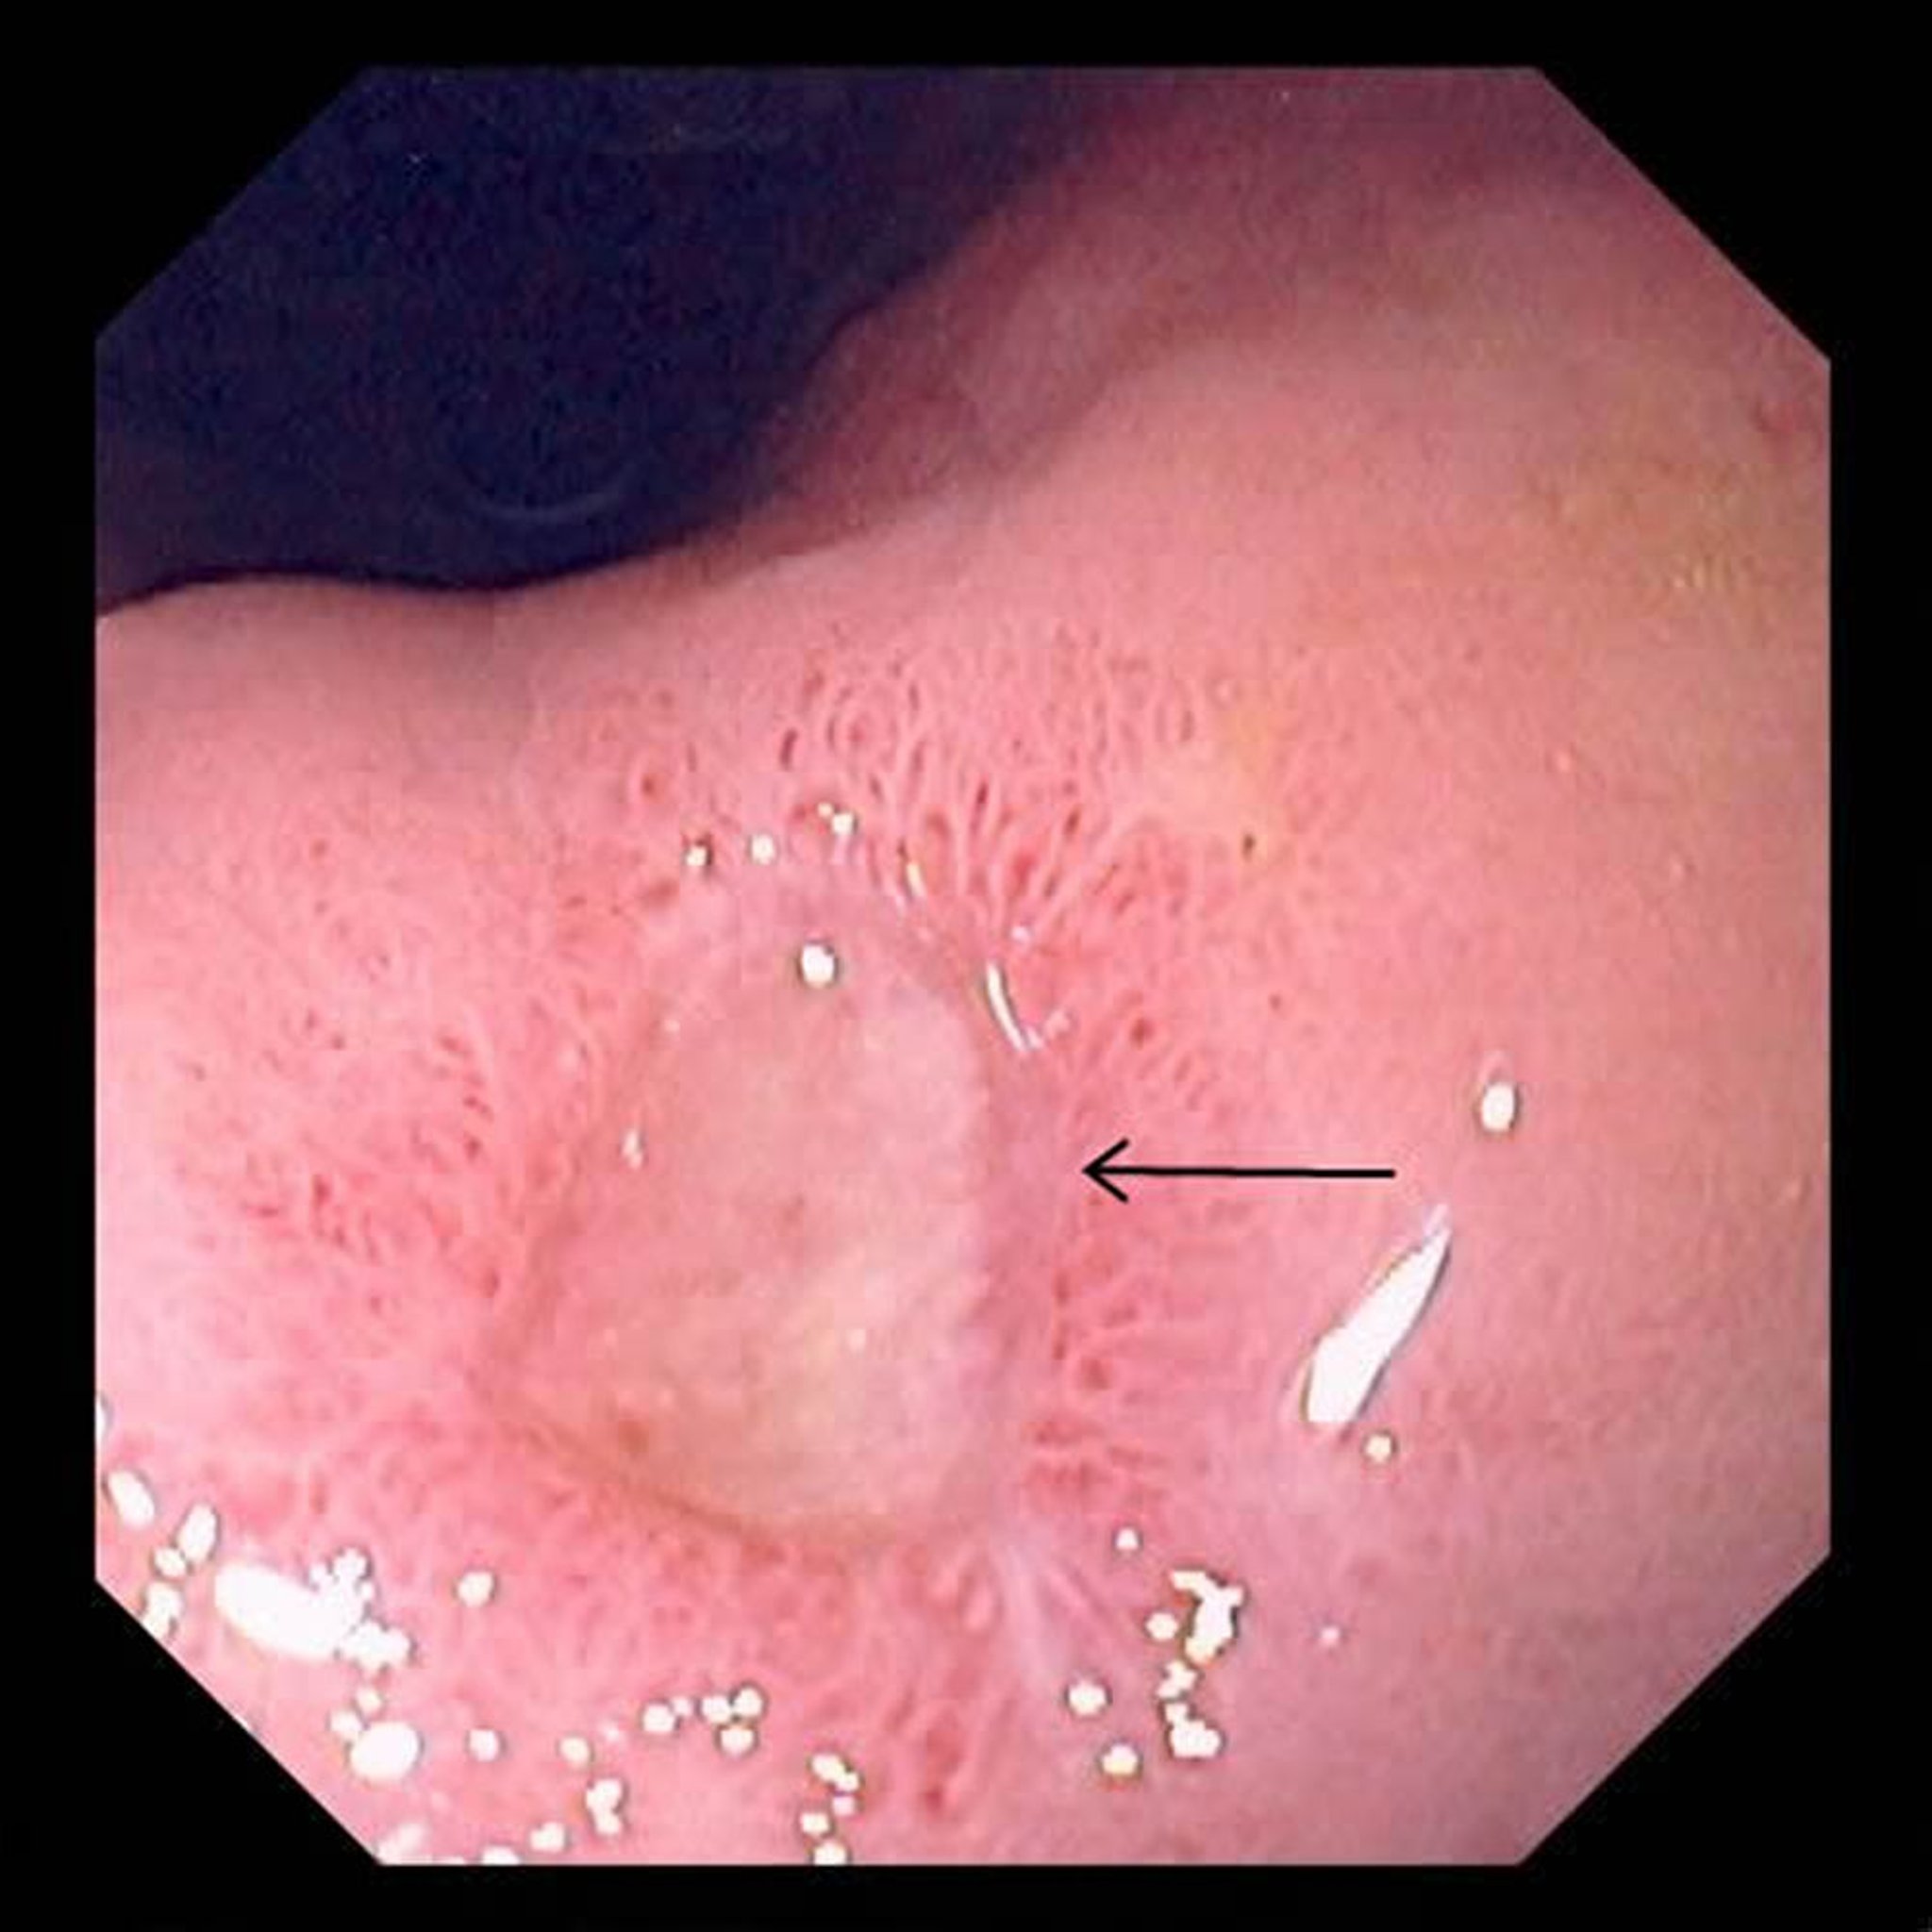

Cette photographie montre un ulcère de grande taille (flèche) dans l’estomac.

Photo fournie par le Dr David M. Martin.